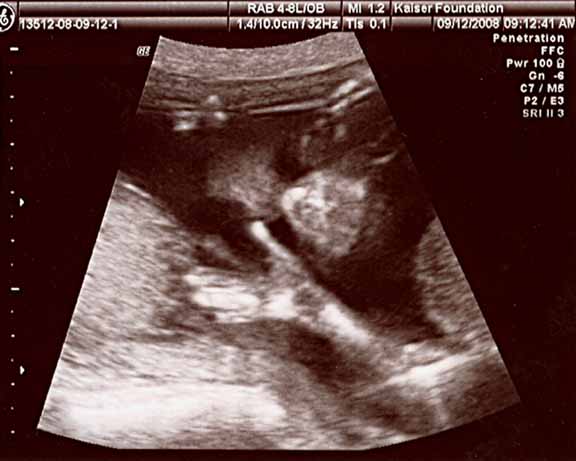

here’s a sonogram of our daughter waving a hand to ya, to be named for my mother, Eleanore